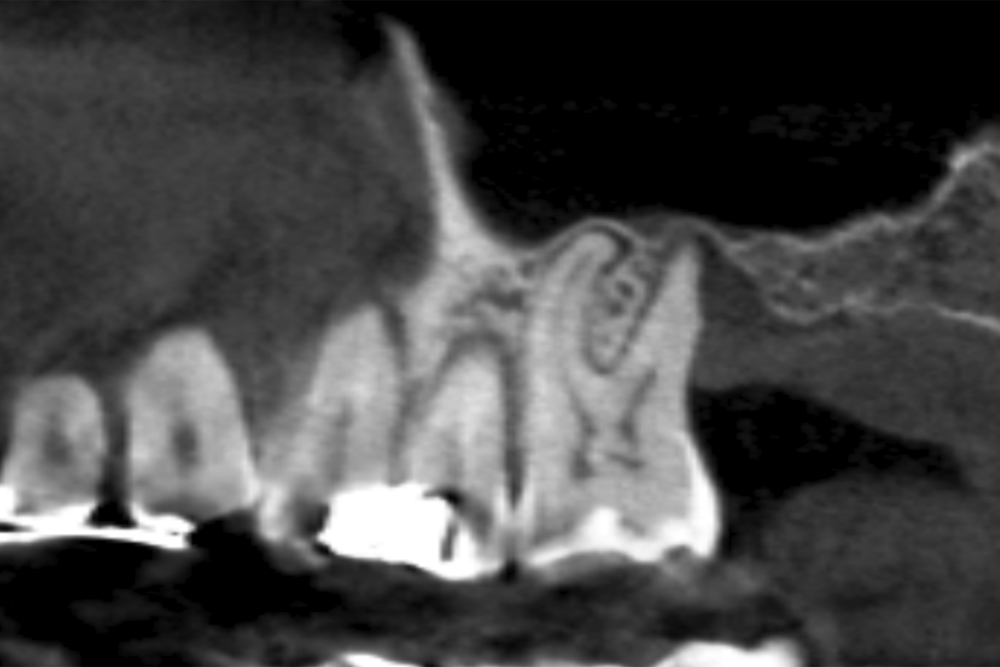

Material and method. A retrospective study has been carried out in patients in whom extra-short implants (4.5 and 5.5 mm length) were inserted directly by transcrestal elevation with residual ridges between 2 and 3 mm. The implant was the analysis unit for the descriptive statistics regarding location, implant dimensions, and radiographic measurements. The patient was the measurement unit for the analysis of age, sex and medical history. The main variable was the gain in height over the apex of the implant after 6 months of the surgery and one year after the load comparing both measurements and as secondary variables the biological complications and the implant failure were recorded.

Results. Ten patients who met the inclusion criteria were recruited and 20 implants were inserted. The mean residual bone volume height was 3.1 mm (+/- 0.3 mm with a range elevation above the apex of the implant in millimetres is of 2.8 mm (+/- 0.99 range 1.9 -5 mm). In the control cone-beam after one year of the studied load of the implants, the bone gain achieved was maintained, with no decrease in the volume gained, only three cases showed a decrease of between 0.4 and 0.5 mm of the initial volume at the end. No implants failed in the follow-up period and no biological complications were found in the surgery.

The crestal lifting technique is currently among the most used to treat the height deficit of the posterior maxilla, when there is a bone remnant of at least 5 mm21-23 in height, although currently there are also research studies that indicate that this technique can be used even if the bone volume is less than this height20-25.

The use of a careful milling technique adapted to the receiving orifice, increasing the primary stability with the diameter of the implant and the anchorage in the vestibular cortex, palatal, mesial and distal (instead of looking for apical anchorage), they are the success keys of these works where extra-short implants have been inserted at residual heights of less than 5 mm even when the residual density was low20-25. In addition, in the follow-up of these implants, no lower success rate or complications related to low residual height or migrations of implants to the maxillary sinus have been 20-25.